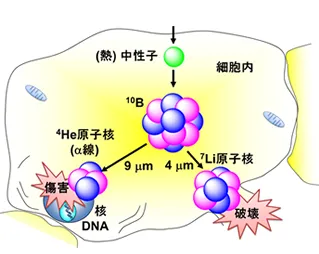

而BNCT则不同,它释放的α粒子射程极短(约一个细胞直径),能量高度集中在含有硼的癌细胞内。因此,它对正常组织的潜在影响,根源不在于射线路径,而在于正常细胞是否“误吸”了硼药——这个概率和量级都极低。

因此,即使患者既往接受过足量放疗,只要复发病灶对硼药物有良好的摄取,BNCT就可以安全地对同一区域进行再次照射。